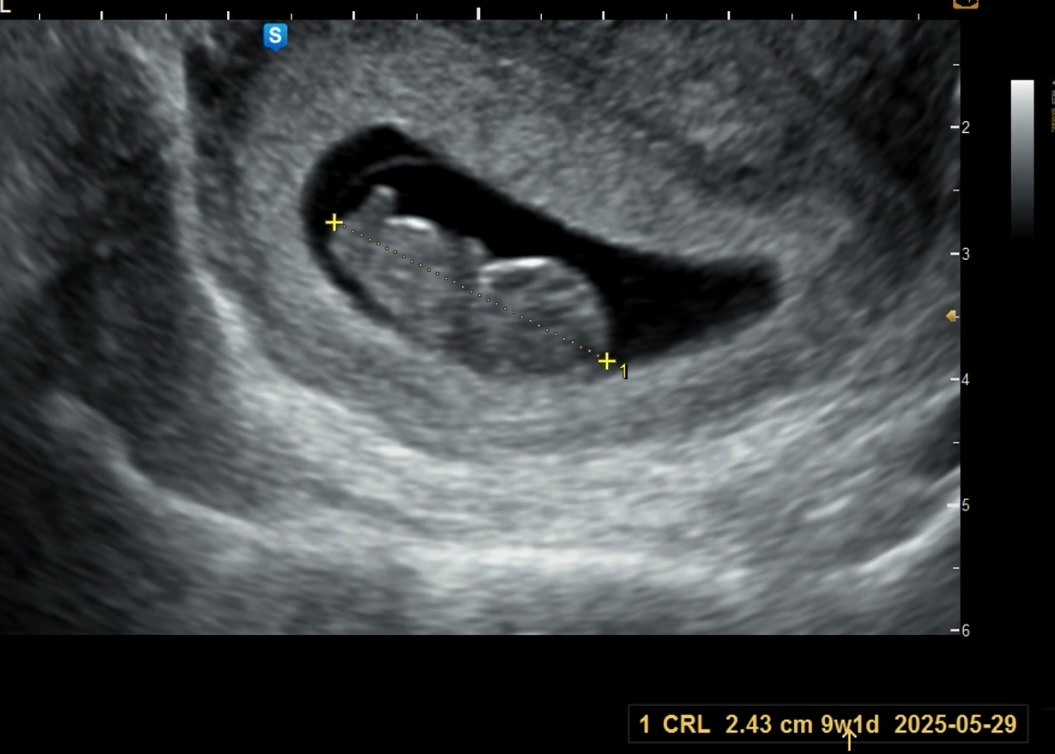

7주차: 아직 잘 안 보인다. 머리가 아니라 난황이라고 설명해 주셨지만 꼭 머리 같아...

9주차: 이때가 너무너무 귀여웠다 ㅠ 젤리곰처럼 꿈틀대던 우리 아기 ㅠㅠ